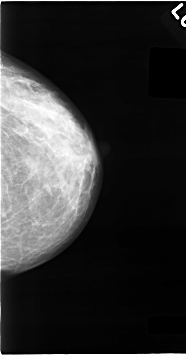

C_0063_1.RIGHT_MLO

ics_version 1.0

filename C-0063-1

DATE_OF_STUDY 6 4 1993

PATIENT_AGE 46

FILM_TYPE REGULAR

DENSITY 3

DATE_DIGITIZED 24 10 1997

DIGITIZER LUMISYS LASER

LEFT_CC LINES 4632 PIXELS_PER_LINE 2416 BITS_PER_PIXEL 12 RESOLUTION 50 NON_OVERLAY

LEFT_MLO LINES 4648 PIXELS_PER_LINE 2512 BITS_PER_PIXEL 12 RESOLUTION 50 NON_OVERLAY